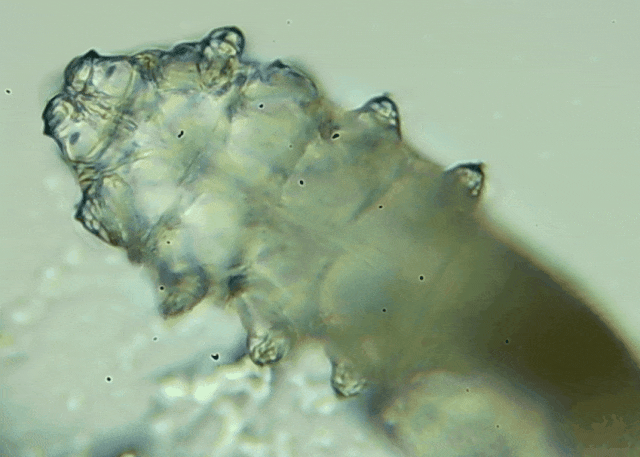

蠕形螨是一類肉眼看不見的寄生螨,常見的有毛囊蠕形螨和皮脂蠕形螨,常駐在人類的毛囊和皮脂腺里,尤其是眼睛的瞼板腺和睫毛根部。數(shù)量少時(shí),蠕形螨能與人體“和平共處”,但一旦你免疫力下降、油脂分泌旺盛或清潔不到位,他們就會(huì)以你難以想象的速度瘋狂繁殖。